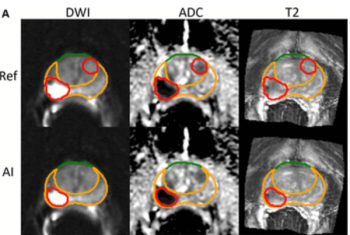

For patients who received radiotherapy for localized prostate cancer, total intraprostatic tumor volume derived from AI segmentation had a 10 percent higher AUC for predicting seven-year metastases in comparison to a risk model from the National Comprehensive Cancer Network (NCCN).